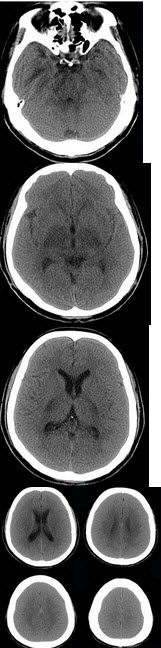

男,57岁,头痛、头晕一周,言语不清,饮水呛咳两天,既往有鼻咽癌病史,给予放射治疗,CT检查如图所示,最可能的诊断为( )

A:脱髓鞘病变

B:脑炎

C:放射性脑病

D:脑梗死

E:胶质瘤